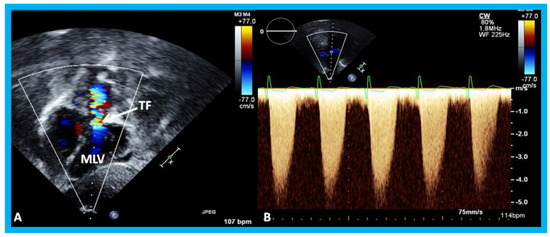

Figure 20. (A) Selected video frame from a subcostal four chamber view (similar to Figure 19B) with color-Doppler demonstrating turbulent flow (TF) in the pulmonary outflow tract. (B) Continuous wave Doppler recording across the pulmonary outflow tract demonstrates peak Doppler velocity of approximately 5 m/sec suggesting significant obstruction. MLV, morphological left ventricle. Reproduced from Yarrabolu T.R., et al. [23].